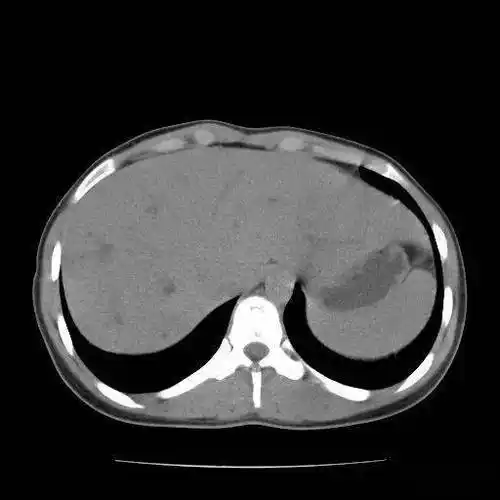

发现肝包虫,县疾控中心上报并确诊为我县域首例上报肝包虫病例.

肝包虫病?肝囊性变?